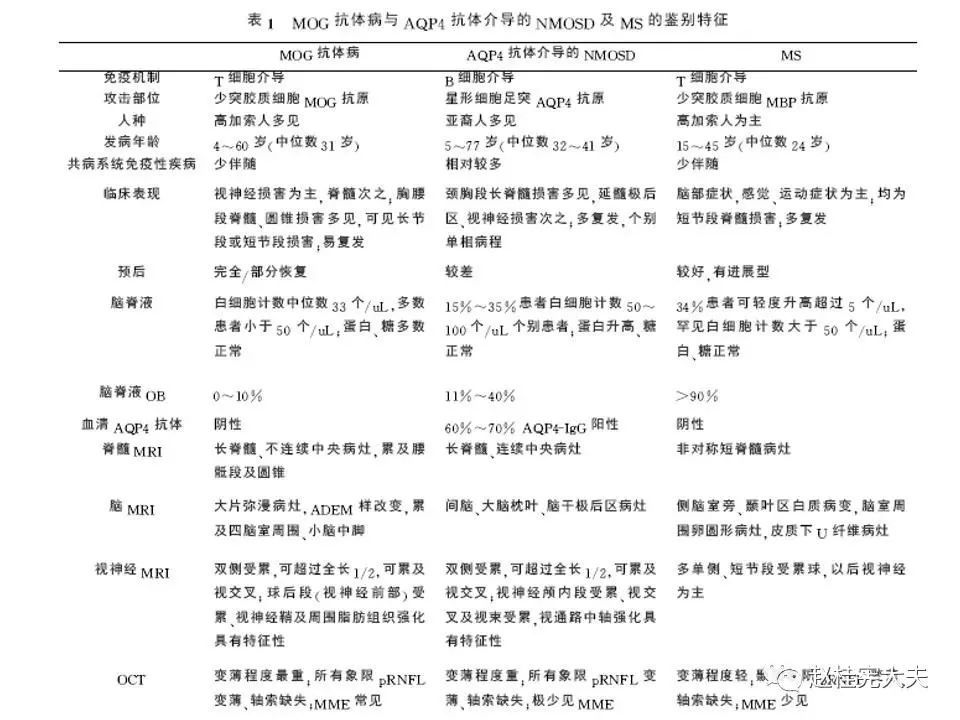

就是一种由MOG抗体介导的中枢神经系统自身免疫性疾病,目前被命名为MOG抗体相关性疾病,即MOGAD,在AQP4抗体未被发现,NMO/NMOSD还没有从MS分离出来时被诊断为MS,当NMO/NMOSD因AQP4抗体的发现从MS分离出后,它被诊断为NMO/NMOSD,在前几年,在一些AQP4抗体阴性的NMOSD患者中发现了MOG抗体阳性,MOG抗体相关性疾病才被认识,曾被命名为MOG脑脊髓炎,终于在2年前正式被命名为MOG抗体相关性疾病,当然,目前还有不少同道还将MOGAD诊断为NMOSD,按照其发病机制和分子靶部位,MOGAD和NMOSD是不同的,应该将其单独列为一个疾病去诊治。(个人意见,欢迎指正和讨论!)